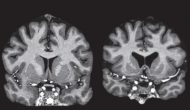

今天哈佛和Broad的科學(xué)家上線了一篇文章(https://www.biorxiv.org/content/10.1101/2020.06.18.159418v1.full),回顧過去5年尋找朊毒體蛋白(PrP)先導(dǎo)物的歷程。

Continue reading …